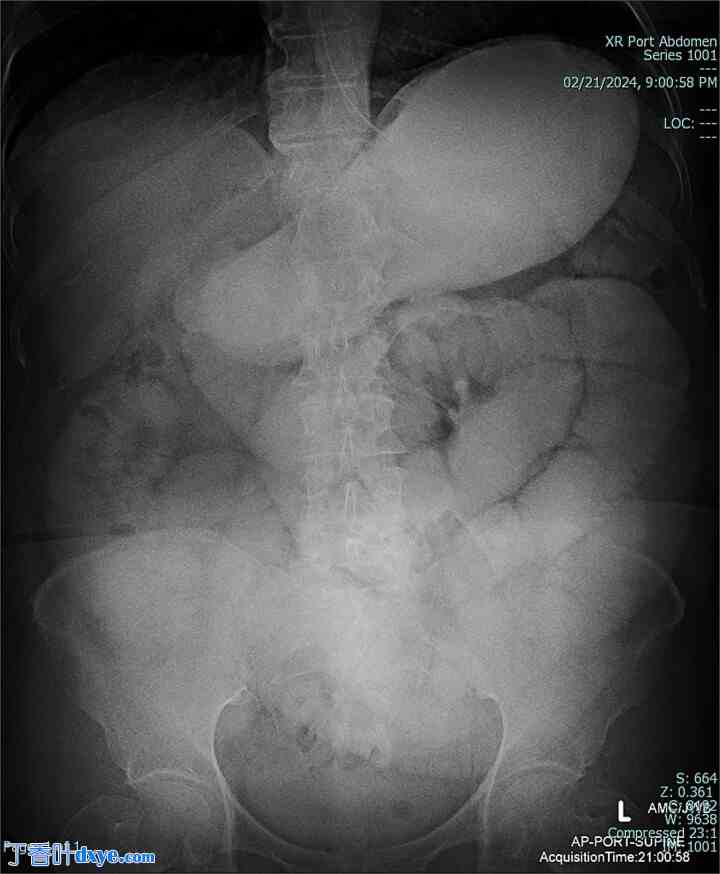

一名 67 岁的女性患者,既往病史仅与剖腹产有关,出现 1 周间歇性腹痛、腹胀和恶心呕吐。生命体征在正常范围内。体格检查发现腹部柔软、无膨胀,右下腹压痛。实验室检查未发现异常。放射影像学(图 1 和图 2)显示小肠梗阻正在发展。

图 1。

术前腹部 X 光片,显示小肠梗阻。